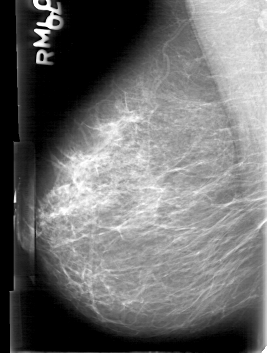

D_4086_1.RIGHT_MLO

RIGHT_CC LINES 5311 PIXELS_PER_LINE 3781 BITS_PER_PIXEL 12 RESOLUTION 43.5 NON_OVERLAY